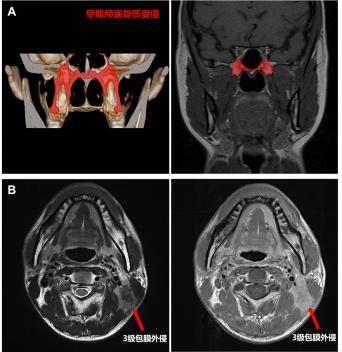

随着核磁共振技术的发展,鼻咽癌早期颅底骨质受侵(仅翼突或蝶骨基底受侵)患者的检出率显著提高,占到所有患者的10-20%,原发灶分期为T3患者的20-30%。既往研究报道早期颅底骨质受侵患者预后较好,或可豁免高强度的化疗。本次研究结果显示,早期颅底骨质受侵的T3患者的5年生存率为91.9%,显著优于其余T3患者(88.8%),且与T2患者相似(91.5%)。因此,建议将轻度颅底骨质受侵降为T2。

颈部严重淋巴结包膜外侵(即3级包膜外侵,肿瘤突破淋巴结包膜侵犯淋巴结周围邻近结构)患者往往临床预后较差,治疗后极易发生复发转移。研究发现原淋巴结分期为N1和N2患者中严重颈部淋巴结包膜外侵患者5年生存率分别为82.0%和77.1%,与N3的78.7%接近。因此,建议严重颈部淋巴结包膜外侵升级为N3。

A早期颅底骨质受侵:仅有翼突或蝶骨基底的颅底骨质受侵

B 3级淋巴结包膜外侵:肿瘤突破淋巴结包膜侵犯淋巴结周围邻近结构